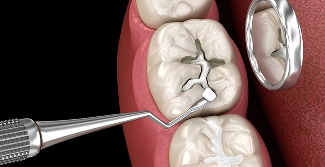

STEP 01

신경치료01

충치 또는 신경이

손상된 치아 확인

STEP 02

신경치료02

충치 제거 및 신경조직

제거 후 신경관 소독

STEP 03

신경치료03

치아 뿌리 내부에

인공 신경 물질 채우기

STEP 04

신경치료04

치아파절 방지를 위한

크라운 보철 씌우기